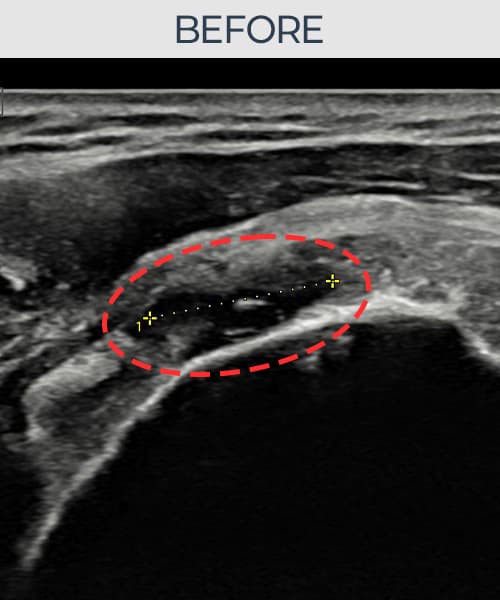

[촬영시기:21.09.02~21.10.07]

[석회분쇄흡입술] 좌측 어깨 통증으로 팔을 옆으로 올리기 어려워진 60대 남성 환자로, X-ray에서 좌측 극상근건 내 석회 침착이 확인되어 석회분쇄흡입술을 시행하였습니다.